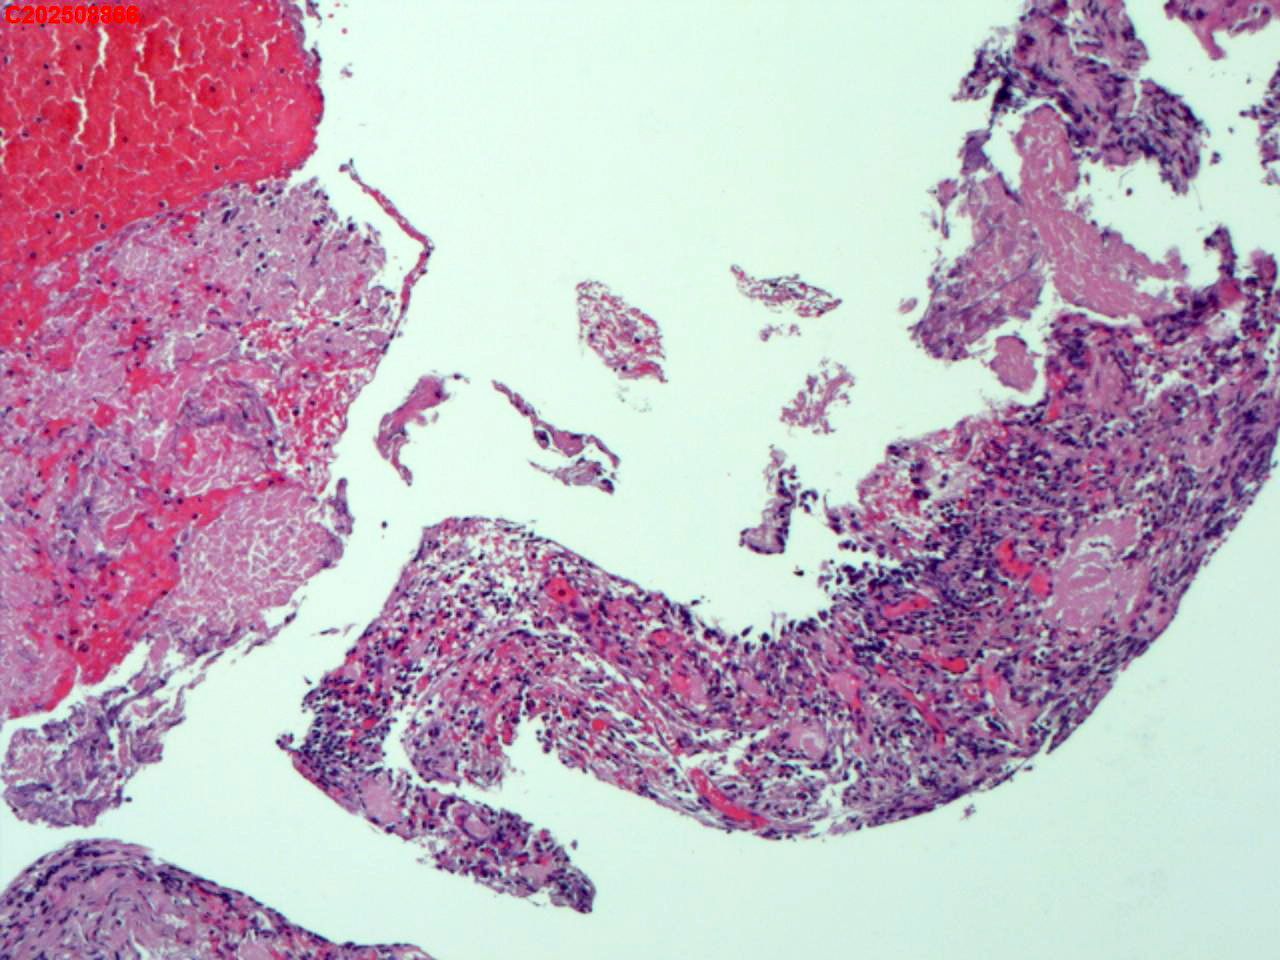

纤支镜咬检

肺TB?Ca?

胸部CT(平扫):考虑双肺感染性病变,结核?支气管炎?请结合临床及其它检查。

标本名称

右肺上叶后段开口咬检组织

大体所见

右肺上叶后段开口处粘膜不规则增生。

肉芽肿性炎的可能性大些!

有坏死,深染变形的细胞需要排一排神经内分泌肿瘤。